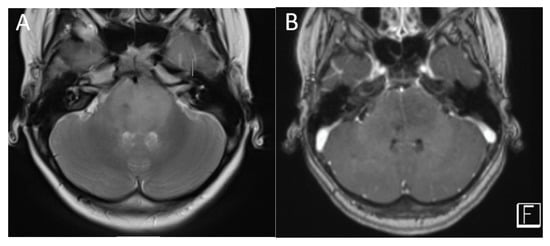

Figure 4.

A 2.5-year-old girl with AT/RT. Axial T2 (A), post-contrast T1 (B), images demonstrate a heterogeneous lesion in the right cerebellopontine angle extending into the internal auditory canal. There is also a metastatic lesion in the left IAC (arrow). DWI (C) and SWI (D) imaging demonstrate restricted diffusion and susceptibility common in these lesions.